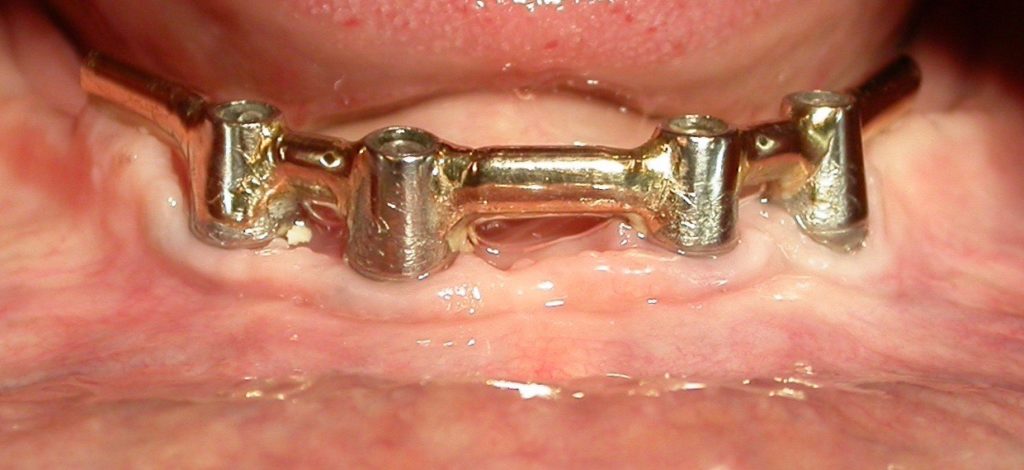

Le contrôle de plaque reste un élément primordial dès le placement d’implants, et lors de la réalisation de la prothèse, il faudra veiller à ce qu’il soit facilité. La connectique idéale est celle qui permettra la meilleure étanchéité pour éviter tout risque de contamination. Le risque de placer des prothèses scellées est la fuite potentielle de ciment.

Une séance de maintenance implantaire doit au moins comprendre une révision de l’anamnèse, un examen clinique et radiologique, un entretien motivationnel, un contrôle occlusal et l’élimination des dépôts durs et mous de toute la bouche. L’instrumentation ultrasonique permet un accès dans les poches autour des implants grâce à des inserts spécifiques en titane. Les aéropolisseurs assurent l’élimination des dépôts mous, certaines buses étant utilisées avec des poudres spécialement conçues pour la zone sous-gingivale.